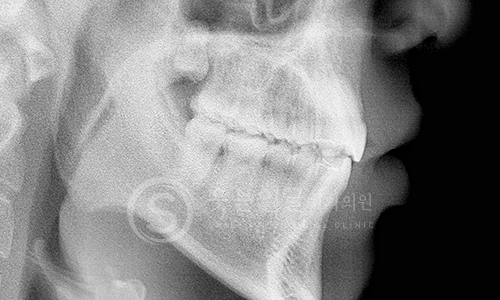

고난이도 임플란트

뼈 이식이나 발치 즉시 식립 등 까다로운 조건에서도 정밀 진단과

체계적인 시술 시스템으로 환자 맞춤형 치료를 제공합니다.

• 고난도 임플란트 전문 진료

웃는얼굴치과는 난이도가 높은

임플란트 수술까지 정밀한 진단과 계획을

바탕으로 안전하게 치료합니다.

• 풍부한 임상 경험과 맞춤 진단

다양한 케이스에서 축적된 풍부한 임상 경험을

토대로, 환자별 구강 상태를 세밀하게 분석하여

최적의 임플란트 수술을 제공합니다.